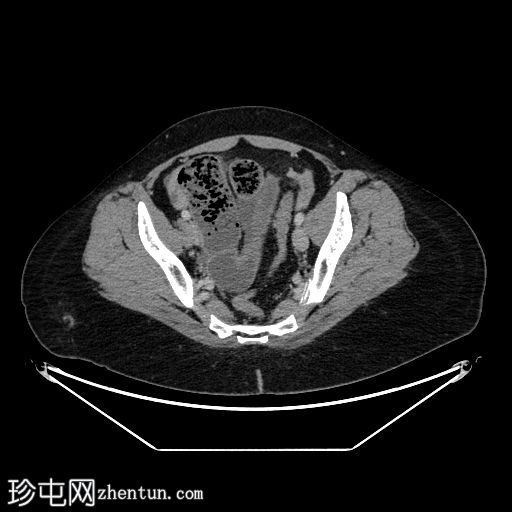

轴位增强扫描(门静脉期)

小肠袢扩张,远端回肠袢可见粪便样改变,提示移行点就在附近。移行点远端可见回​​肠塌陷。

在移行点近端,肠系膜对侧缘可见一盲端管状结构,符合梅克尔憩室的特征。

少量游离液体。